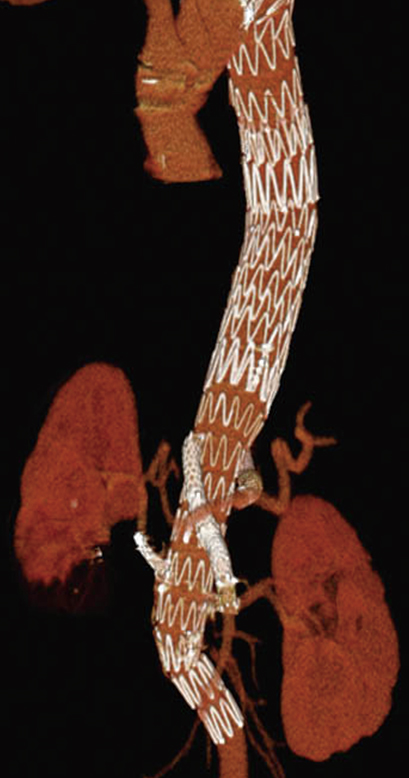

ステントグラフト内挿術

こぶになって弱くなった大動脈部分の中にパイプ状の人工血管を差し込んで固定し、弱くなった大動脈壁に直接血圧がかからないようにする方法です。開腹しないため、体にかかる負担が小さいのが利点です。一方で動脈瘤の形状によっては人工血管(ステントグラフト)がフィットしない場合があり、全ての症例には対応できないこと、追加治療が必要になる場合があることが欠点です。